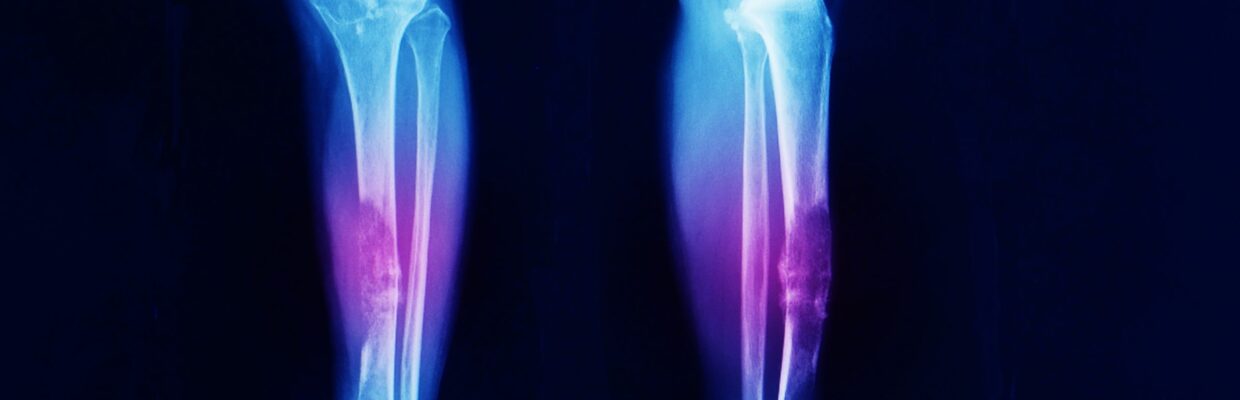

- radiologists (x-ray and scans)